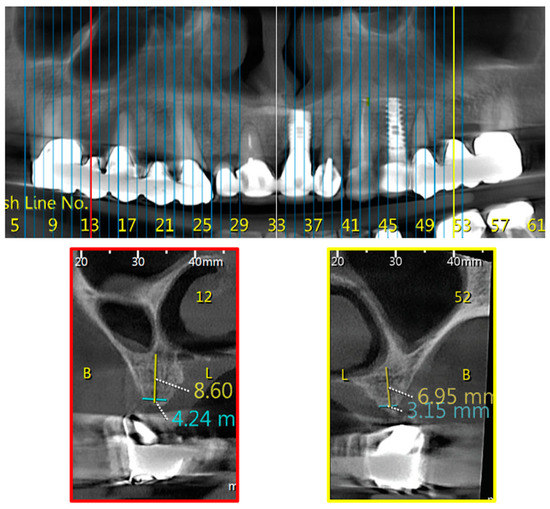

Immediate Implant and Customized Healing Abutment for a Periodontally Compromised Socket: 1-Year Follow-Up Retrospective Evaluation

by Giovanni-Battista Menchini-Fabris, Saverio Cosola, Paolo Toti, Myoung Hwan Hwang, Roberto Crespi and Ugo Covani

Immediate dental implant placement with or without immediate loading is reported in daily dentistry and implantology, but these procedures are not common in the case of periradicular and periapical lesions around the tooth needed to be replaced. In the following retrospective evaluation, 10 [...] Read more.

Immediate dental implant placement with or without immediate loading is reported in daily dentistry and implantology, but these procedures are not common in the case of periradicular and periapical lesions around the tooth needed to be replaced. In the following retrospective evaluation, 10 cases with a 1-year follow-up were selected to propose the technique of an immediate provisional non-loading prosthesis being delivered on the same day of the post-extraction implant placement in multiradicular teeth affected by chronic periradicular and periapical lesions. Post-extractive sockets underwent immediate dental implant placement by filling the empty space with sterile, re-absorbable gelatin sponges. The widths of the alveolar ridge were measured on three-dimensional radiographs before and after the operation, 4 and 12 months later. Non-parametric statistics were performed to compare the outcomes over time with a level of significance of 0.05. Comparing the preoperative cross-sectional images of cone beam computerized tomography (CBCT) scans to the postoperative ones, it was noted that changes in the crestal ridge width, ΔCW, (compared to baseline) were negligible and not clinically appreciable. However, while ΔCW at 4 months appeared to be negative (−0.17 ± 045 mm), crestal width at 12 months was at the same level as the baseline (ΔCW = 0.02 ± 0.48 mm), with a significant difference between 4 and 12 months (p-value = 0.0494). Immediate implant placement with an immediate non-loading provisional customized healing abutment of polyether-ether-ketone placed into the post-extractive sockets with asymptomatic and large chronic periapical and periradicular lesions could represent a further treatment strategy for patients’ rehabilitation and soft tissue preservation to replace a hopeless tooth. Full article